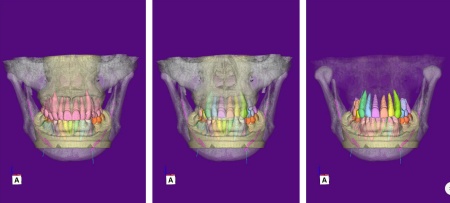

まずは、口腔内全体の矯正治療から開始します。

上顎は左上の歯が欠損していたため、左右のバランスを整える目的で、右上の歯(第1小臼歯)を抜きました。

その後、ワイヤー矯正とクローズドコイル(バネの装置)を使ったスピード矯正を行い、前歯を後方に移動させます。

下顎は残根も利用しながら、矯正用の小さなネジ「テンポラリーインプラント(インプラントアンカー)」を顎の骨に埋め込んで固定源とする方法も併用し、歯を移動させました。

矯正期間中は定期的に装置の調整を行い、歯の動きや噛み合わせの変化を確認しながら治療を進めています。